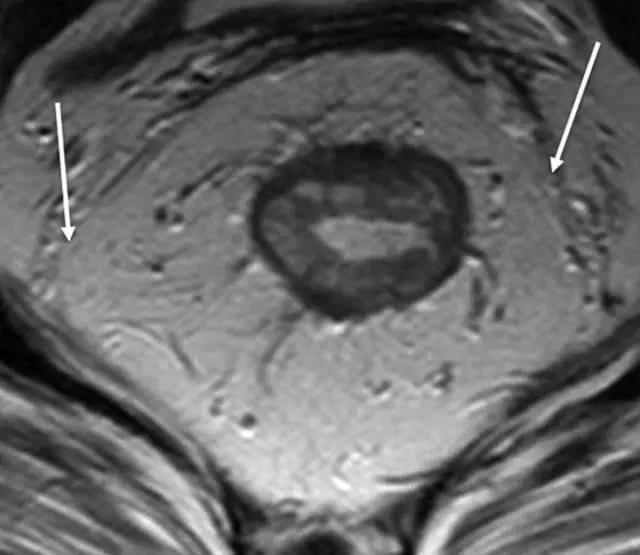

72 岁直肠癌男性,T2 加权轴位图显示 T1 肿瘤,紧邻肿瘤的粘膜下层消失而固有肌层完整。

62 岁直肠癌男性,T2 加权轴位图像显示 T2 期,环形肿瘤侵犯但未超过肌层。